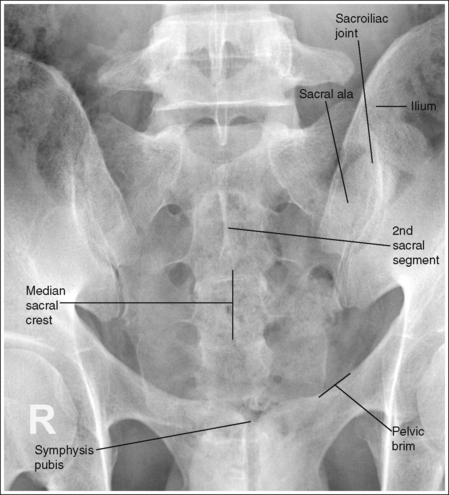

See Figures 7-21 and 7-22 and Box 7-5.

The pelvis demonstrates an AP projection. The ischial spines are aligned with the pelvic brim, the sacrum and coccyx are aligned with the symphysis pubis, and the ilia and obturator foramina are open and uniform in size and shape.

• An AP projection of the pelvis is accomplished by placing the patient supine on the imaging table, with the legs extended and the arms drawn away from the pelvic area (Figure 7-23). To ensure that the pelvis is not rotated, judge the distance from the ASIS to the imaging table on each side. The distances should be equal.

• Pelvic rotation. A nonrotated AP pelvis projection demonstrates symmetrical ilia and obturator foramina. Rotation is initially detected by evaluating the relationships of the ischial spines with the pelvic brim and of the sacrum and coccyx with the symphysis pubis. The ischial spines should be aligned with the pelvic brim, and the sacrum and coccyx should be in alignment with the symphysis pubis on a nonrotated pelvis. If the pelvis is rotated into a LPO position, the left ilium is wider than the right, the left obturator foramen is narrower than the right, the left ischial spine is demonstrated without pelvic brim superimposition, and the sacrum and coccyx are not aligned with the symphysis pubis but are rotated toward the right hip (see Image 16).

• If the patient was rotated into a right posterior oblique (RPO) position, the opposite is true. The right ilium is wider than the left, the right obturator foramen is narrower than the left, the right ischial spine is demonstrated without pelvic brim superimposition, and the sacrum and coccyx are rotated toward the left hip.

The femoral necks are demonstrated without foreshortening and the greater trochanters are in profile laterally, whereas the lesser trochanters are superimposed by the femoral necks.

• Accurate leg positioning. To demonstrate the femoral necks without foreshortening and the greater trochanters in profile on an AP pelvis projection, the patient's leg should be internally rotated until the feet are angled 15 to 20 degrees from vertical and the femoral epicondyles are positioned parallel with the imaging table (Figure 7-24; see Figure 7-21). Sandbags or tape may be needed to help maintain this internal leg rotation. An AP pelvis projection may not demonstrate the proximal femurs with exactly the same degree of internal rotation. How each proximal femur appears will depend on the degree of internal rotation placed on that leg.

• Poor leg positioning. The relationship of the patient's entire leg to the imaging table determines how the femoral necks and trochanters are shown on an AP pelvis projection. In general, when patients are relaxed, their legs and feet are externally (laterally) rotated. On external rotation, the femoral necks decline posteriorly (toward the table) and are foreshortened on an AP pelvis projection. Greater external rotation increases the posterior decline and foreshortening of the femoral necks. If the patient's legs are externally (laterally) rotated enough to position the feet at a 45-degree angle and an imaginary line connecting the femoral epicondyles at a 60- to 65-degree angle with the imaging table, the femoral necks are demonstrated on end and the lesser trochanters are demonstrated in profile (Figure 7-25; see Image 17). If the patient's legs are positioned with the feet placed vertically and an imaginary line connecting the femoral epicondyles at approximately a 15- to 20-degree angle with the imaging table, the lesser trochanter is demonstrated in partial profile and the femoral neck is only partially foreshortened (see Image 18).

The inferior sacrum is at the center of the exposure field. The ilia, symphysis pubis, ischia, acetabula, femoral necks and heads, and greater and lesser trochanters are included within the collimated field.

• Center a perpendicular central ray to the midsagittal plane at a level halfway between the symphysis pubis and the midpoint of an imaginary line connecting the ASIS to place the inferior sacrum in the center of the exposure field. Center the IR to the central ray and open the longitudinal collimation the full 14-inch (35-cm) IR length for most adult patients. Transversely collimate to within 0.5 inch (1.25 cm) of the lateral skin line.

• A 14- × 17-inch (35- × 43-cm) IR placed crosswise should be adequate to include all the required anatomic structures.